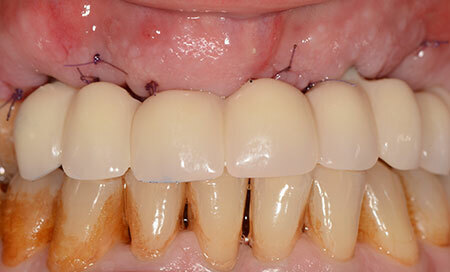

Le bridge fixe provisoire sur 4 implants est remis au patient 5 jours après la chirurgie d’extraction-implantation immédiate complétée par des régénérations osseuses guidées.

Les fistules infectieuses commencent à disparaître et l’aspect gingival est satisfaisant. Les dents mandibulaires sont teintées par la chlorhéxidine prescrite après la chirurgie.